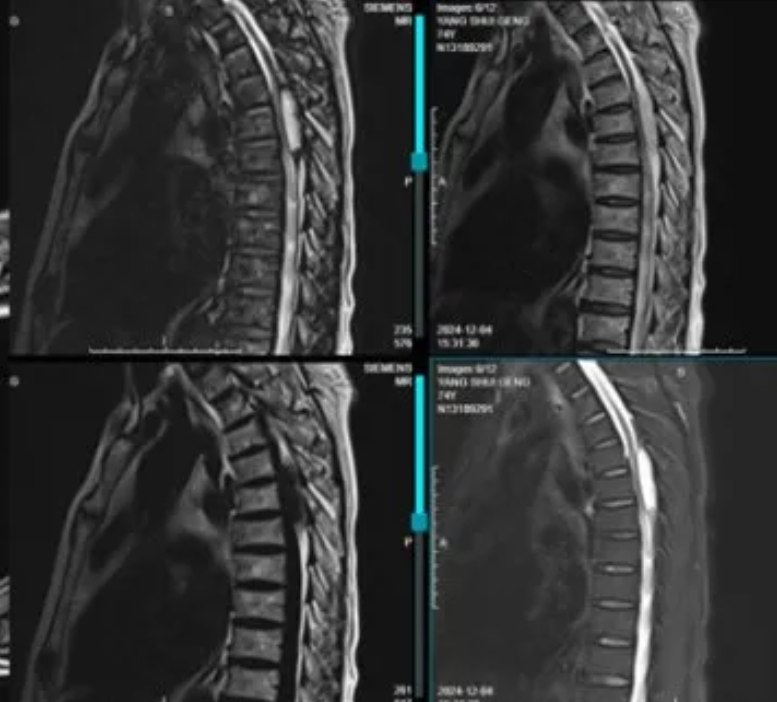

术后随访

患者的疼痛、双下肢乏力,踩棉花感症状完全缓解。患者恢复正常生活。

术后2个月随访